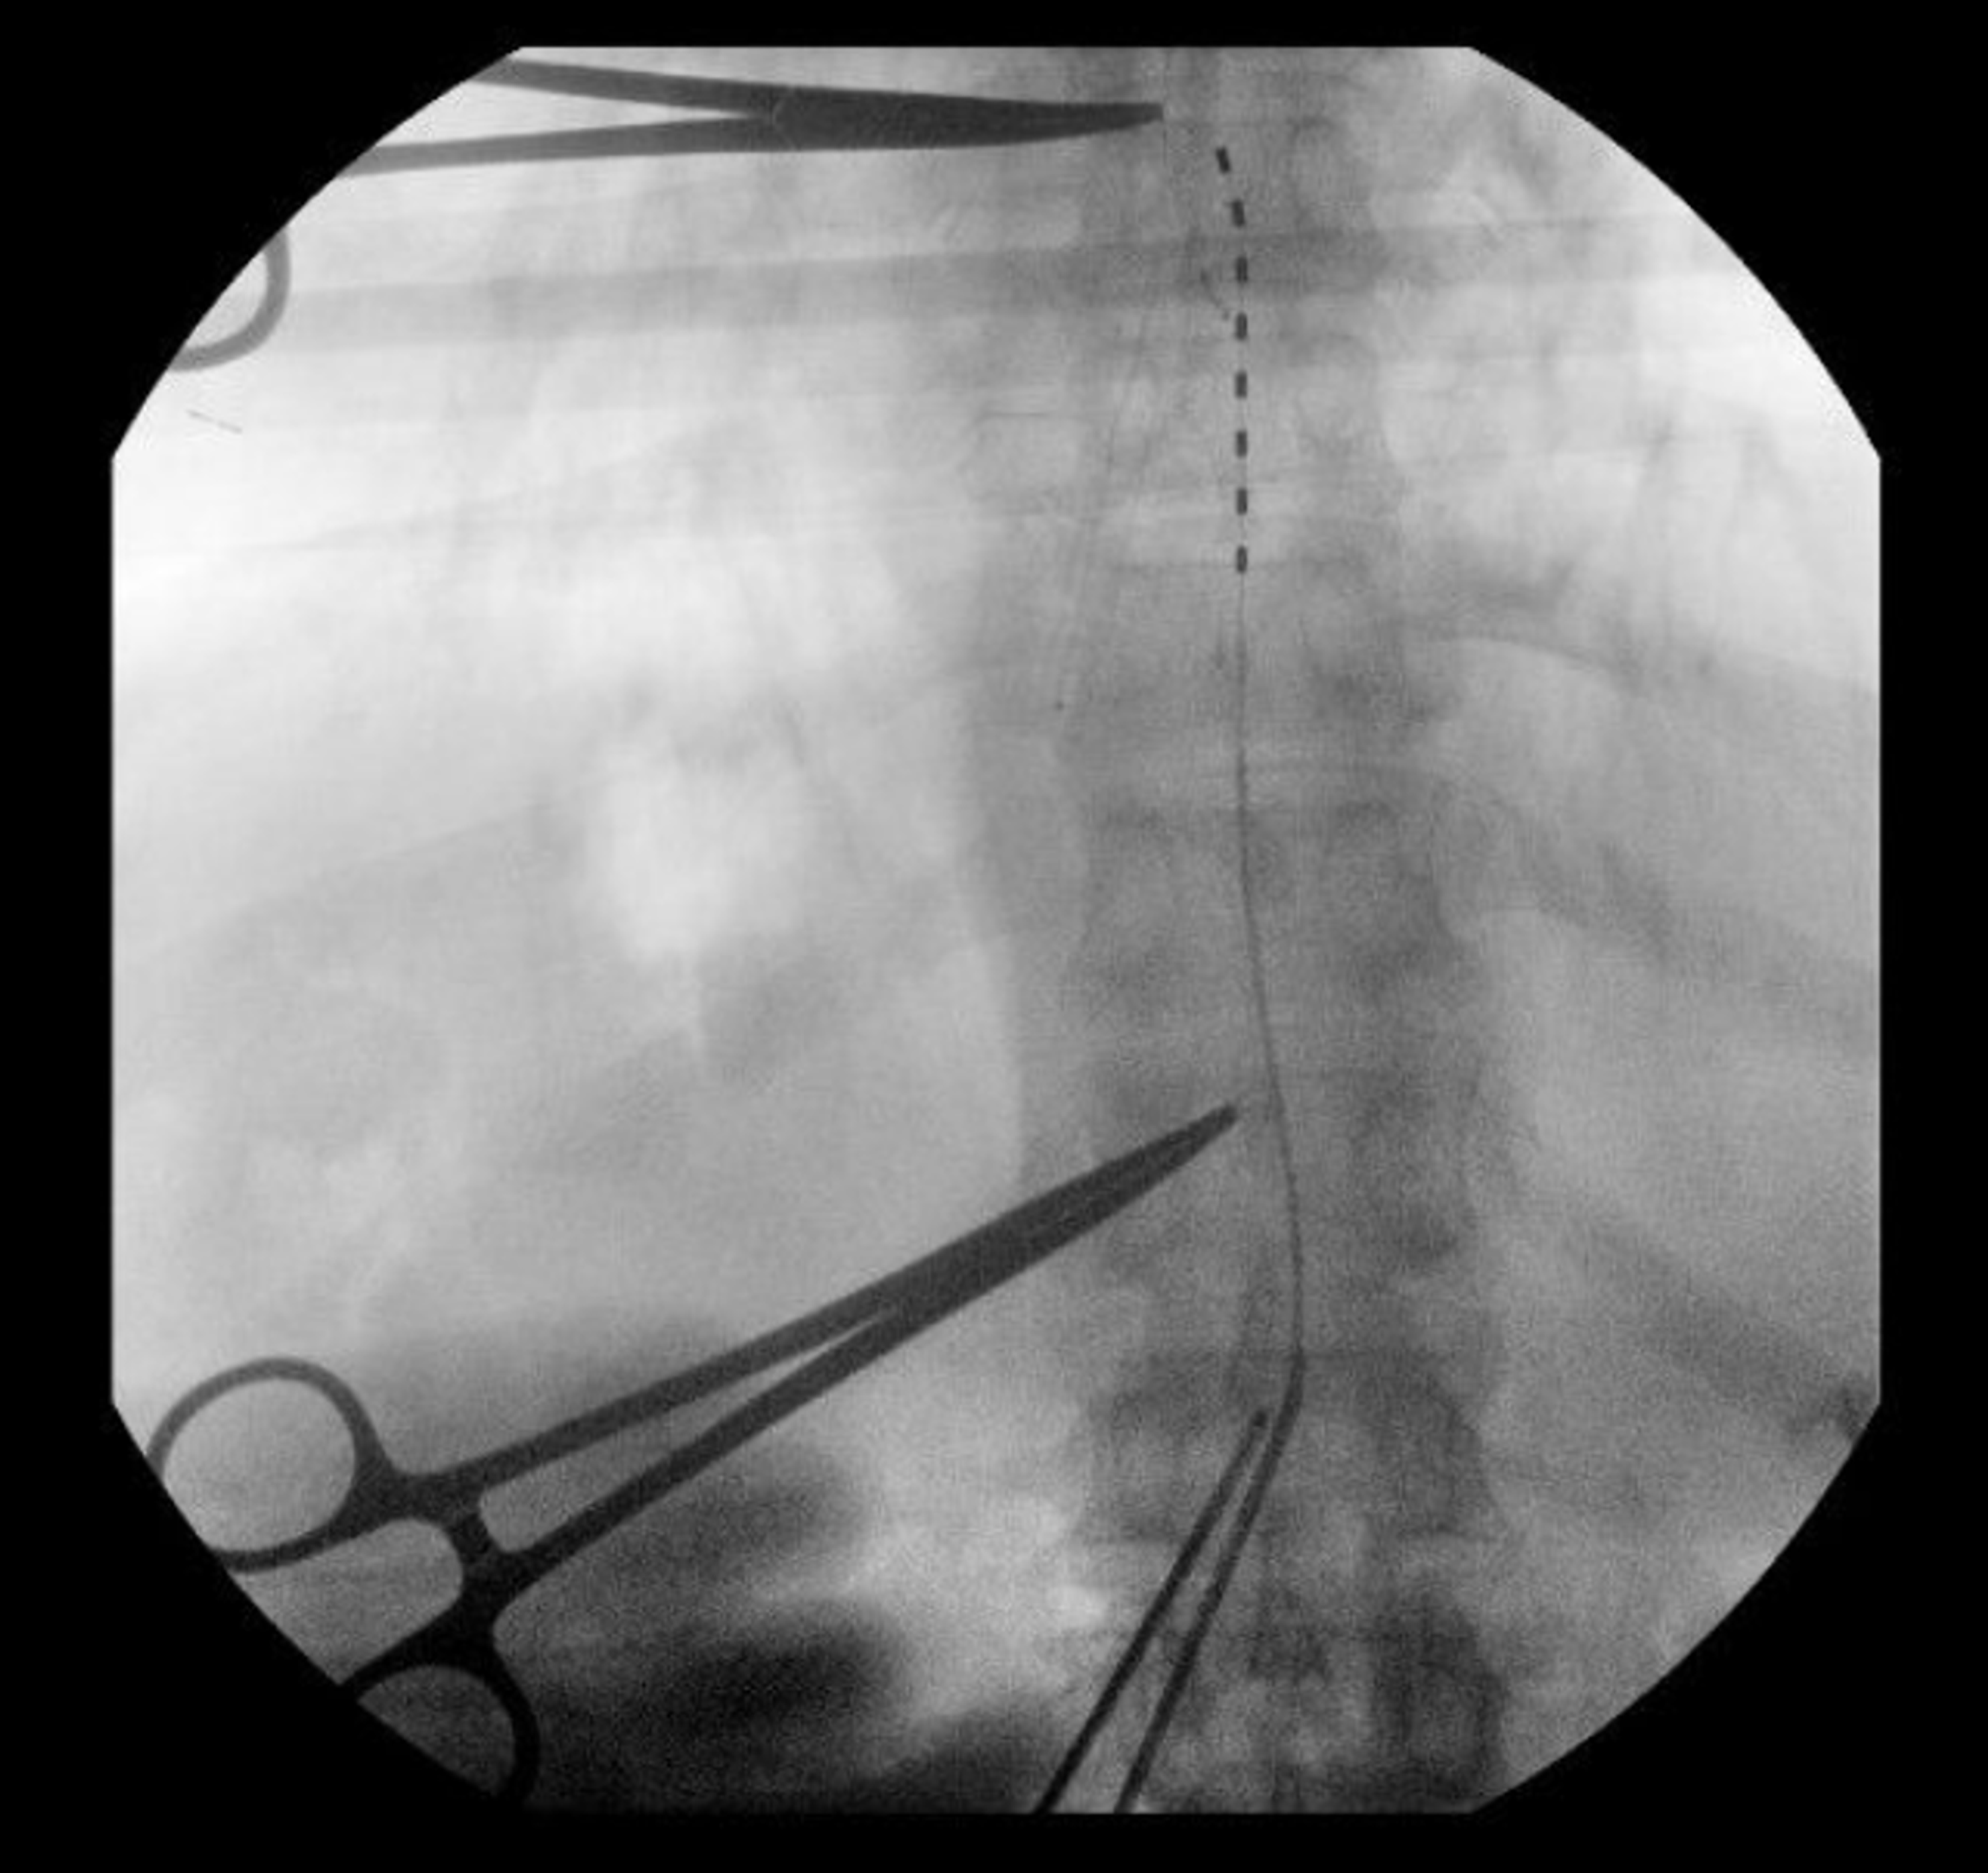

From www.researchgate.net

Two low thoracic spinal cord stimulator leads. Download Scientific Diagram Spinal Cord Stimulator For Thoracic Pain Spinal cord stimulators are implanted devices that help block pain signals from your brain. Thoracic spinal cord stimulation is a treatment modality in which the pain signals are masked before they get a chance to reach the brain. Additionally, as with any surgical implant procedure, there is a. Spinal cord stimulator implantation is a minimally invasive procedure that involves inserting. Spinal Cord Stimulator For Thoracic Pain.

Xray showing spinal cord stimulator system implanted trough thoracic... Download Scientific Spinal Cord Stimulator For Thoracic Pain A spinal cord stimulator is an implanted device that sends low levels of electricity directly into the spinal cord to relieve pain. Thoracic spinal cord stimulation is a treatment modality in which the pain signals are masked before they get a chance to reach the brain. Spinal cord stimulator implantation is a minimally invasive procedure that involves inserting wires near. Spinal Cord Stimulator For Thoracic Pain.